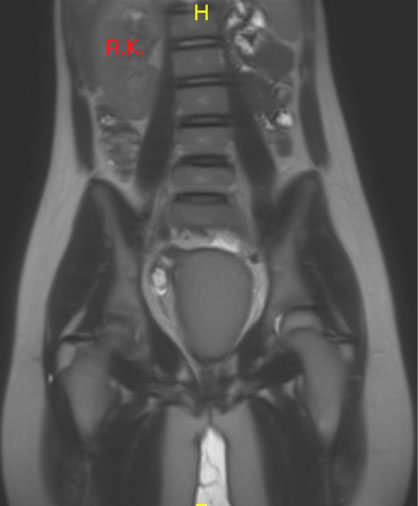

Pelvic MRI showed uterus Didelphis with two hemi-uteri and two hemi-vaginas, the left hemi-vagina was blind, (Figure 1), left hematometro-colpos, and hematosalpinx overlying the dome of the urinary bladder (Figure 2 and Figure 3), Also, it showed left renal agenesis (Figure 4).

Figure 4: MRI image coronal view.

Demonstrating the absence of left kidney. View Figure 4